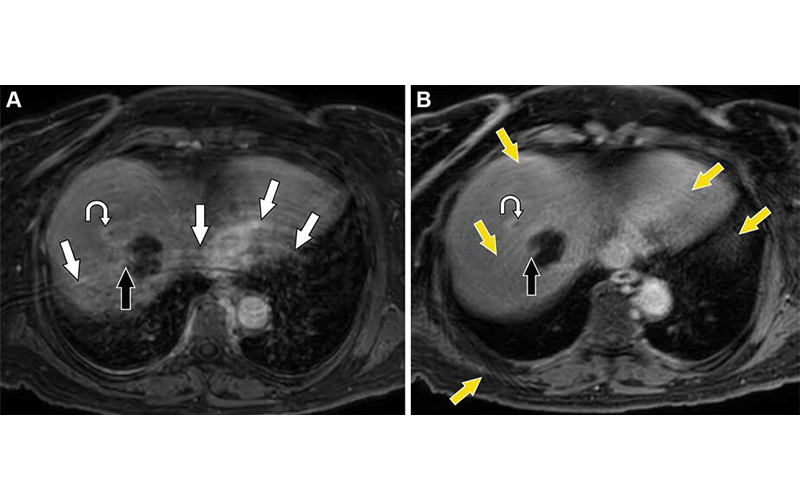

Comparison of postcontrast Cartesian BH and radial k-space free-breathing techniques during the equilibrium phase in a 63-year-old woman 6 months after radiofrequency ablation of hepatocellular carcinoma in the right hepatic lobe. (A) Axial contrast-enhanced Cartesian 3D T1W Dixon image with poor patient BH shows curvilinear aliasing artifacts (white arrows) that raise the question of nodular enhancement at the margin of the treatment zone, suggestive of residual tumor (black arrow). (B) Axial free-breathing radial k-space image, which required 3 minutes and 10 seconds of additional imaging, was performed immediately after the BH series. The curved arrow in A and B denotes a peripherally enhancing satellite nodule with washout (site of hepatocellular carcinoma recurrence), which is better seen on the radial image. Motion artifacts in the form of streaks are present in B (yellow arrows). However, these artifacts are less impactful than the aliasing artifacts seen in A. The suspicious finding at the margin of the treatment zone on the Cartesian image represents a small portion of nonneoplastic hepatic tissue (black arrow). Also, note the overall increased blur in B compared with that in A. 3-T BH GRE Dixon imaging parameters: TR, 3.5 msec; TE, 1.32/2.3 msec; flip angle, 10°; section thickness, 3.2 mm; acquisition matrix, 200 × 200. 3-T free-breathing GRE Dixon radial imaging parameters: TR, 4.8 msec; TE, 1.4/2.7 msec; flip angle, 10°; section thickness, 3.2 mm; acquisition matrix, 300 × 572. https://doi.org/10.1148/rg.230173 © RSNA 2024